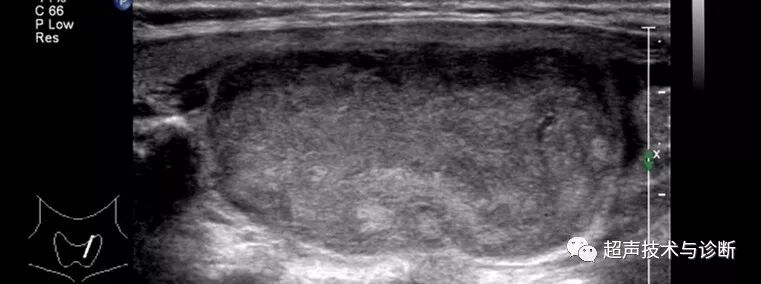

1 甲状腺内圆形或椭圆形均质低回声或等回声结节,一般为单发,边缘规整,周边可见完整包膜,部分结节周边可见厚薄均匀的晕环。

(图2)甲状腺滤泡型腺瘤,甲状腺内椭圆形低回声结节,边界清楚